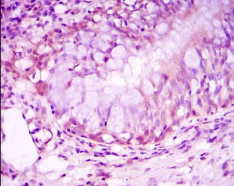

IHC    1/200 - 1/1000